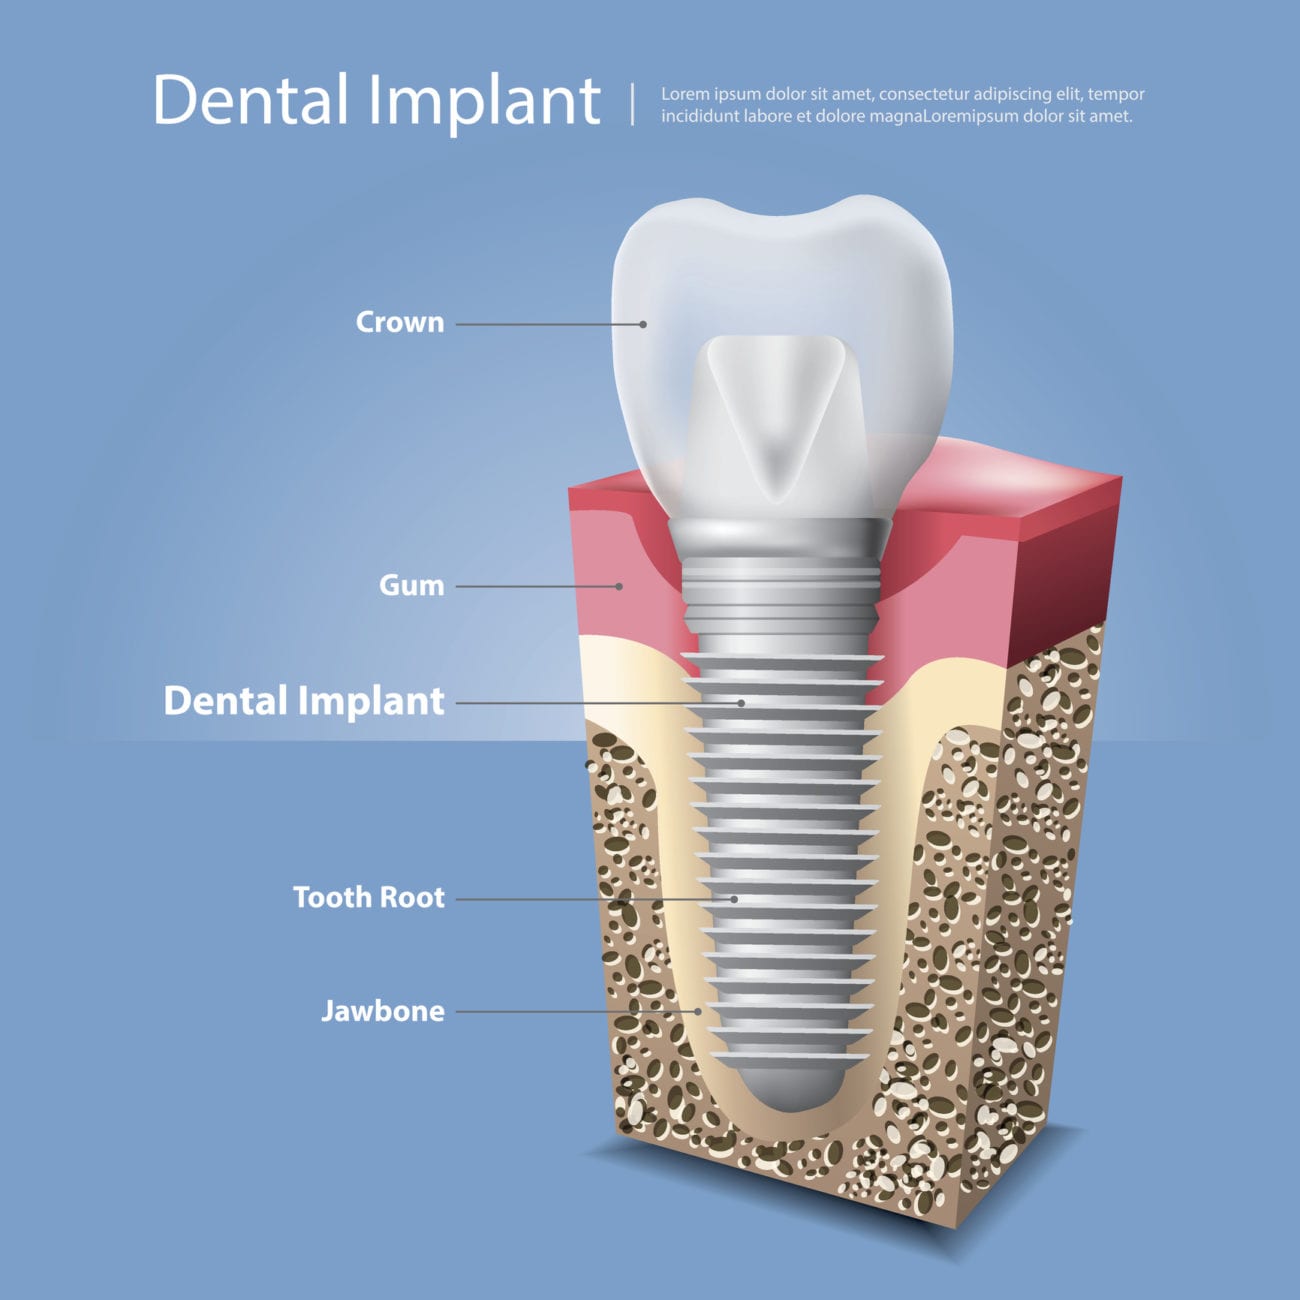

The Anatomy of The Dental Implant | Knoxville TN Dentist

What is a Dental Implant? | DDi

Dental Implant, Single Tooth

How dental implants work – Dental News Network

How do dental implants work? ⋆ Dental House

Dental Implants Portland OR | What Are Dental Implants